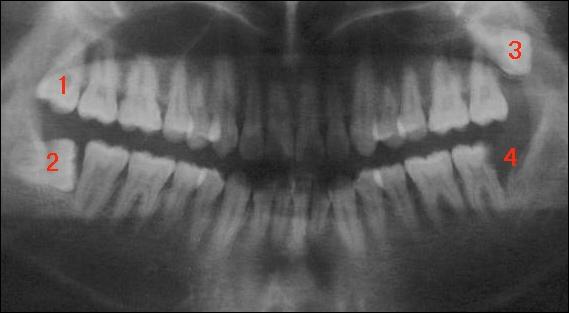

由于人類的進(jìn)化,上下頜骨沒有更多的空間留給我們長牙,因此,智齒經(jīng)常的會長不好,容易出現(xiàn)阻生的情況。什么是阻生,就是阻礙生長。智齒以不同的方式阻礙前牙(第二磨牙,第7顆牙)的生長,從而導(dǎo)致經(jīng)常的發(fā)炎,也就是智齒冠周炎。大家看下面這張圖:

全口曲面斷層片,俗稱骷髏片

圖1位置的智齒正常生長;而下面圖2位置的牙則頂著著面的牙生長,稱為水平阻生;圖3位置的牙飛出來了,稱為垂直阻生;圖4的牙可能拔了,處于空缺狀態(tài)。因此,存在的三顆智齒都必須要拔。如果圖2的牙長的很好,那么1、2可不用拔,但只要上、下有一顆牙沒長好,那這兩顆牙全要拔。